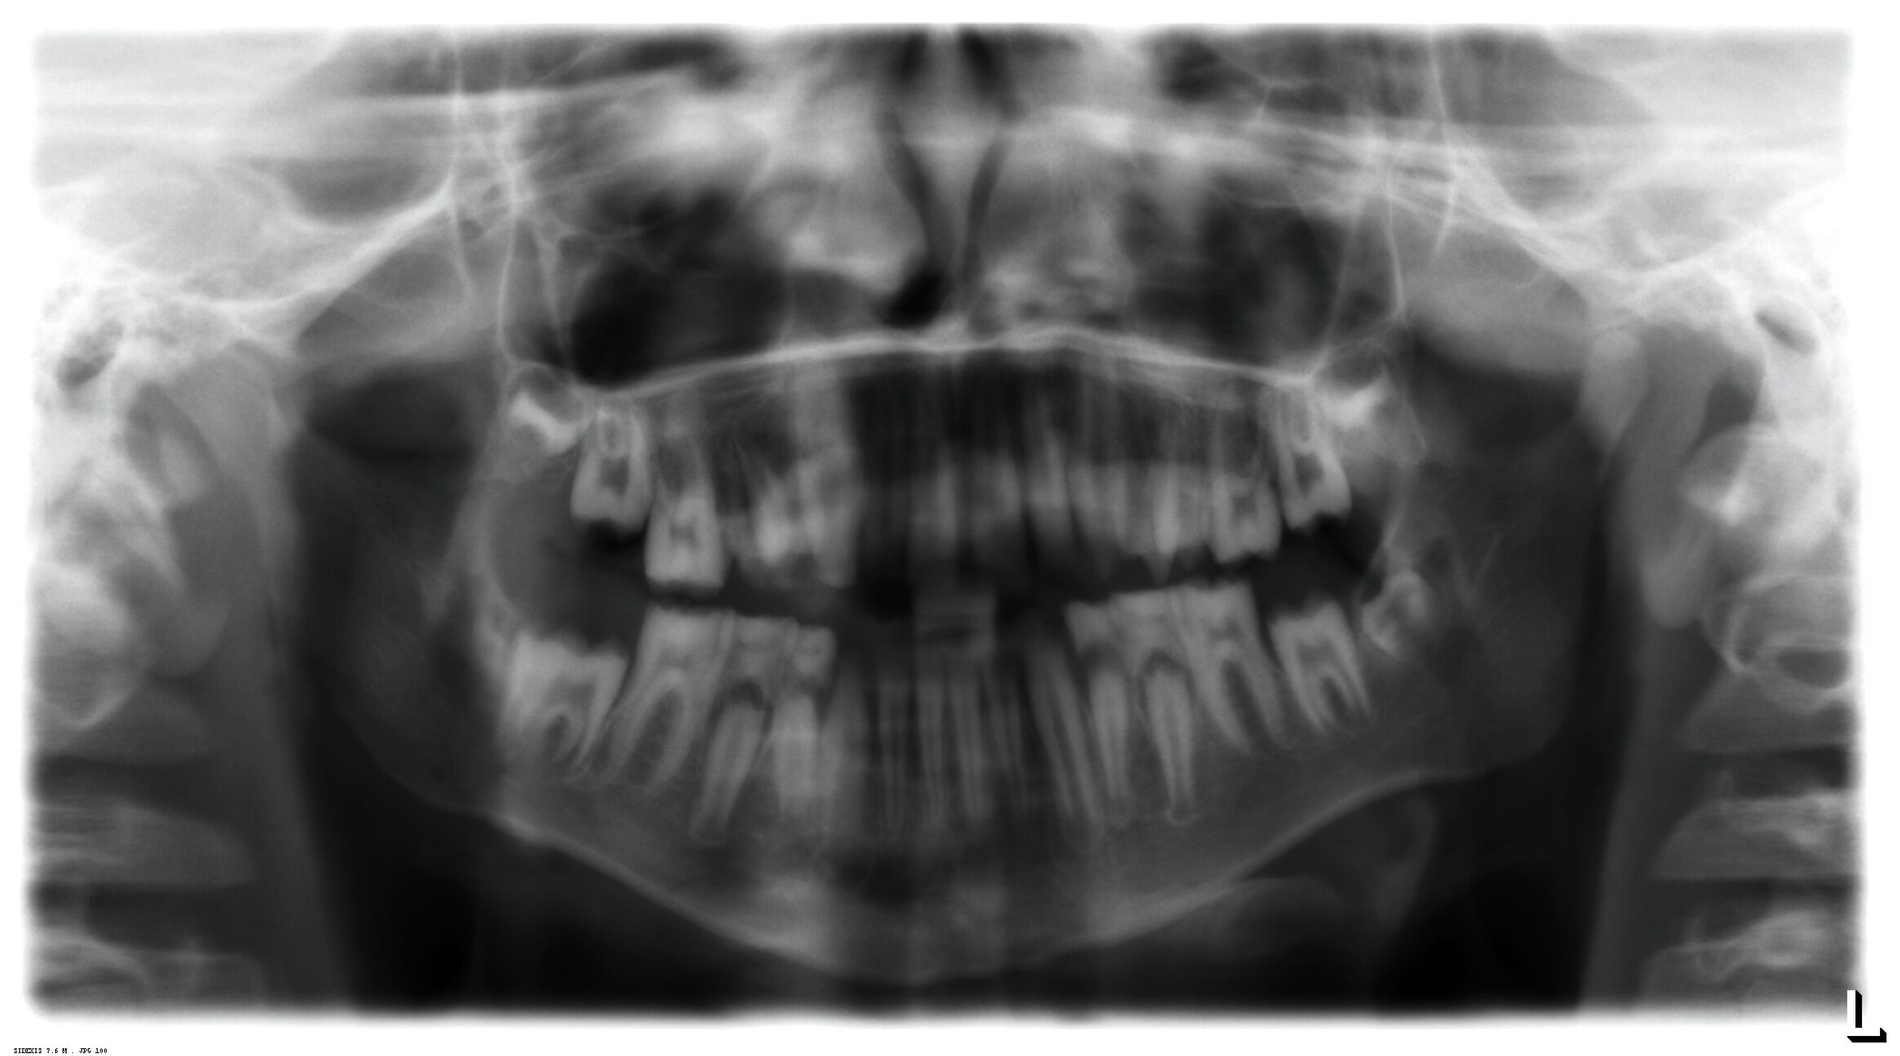

Klinisch zeigte sich ein kariöses Wechselgebiss mit generalisierten Verfärbungen und rauer Schmelzoberfläche. Mehrere Milch- und bleibende Zähne wiesen aktive kariöse Läsionen auf. Zahn 64 war zusätzlich druckdolent und gelockert, mit einer vestibulären Schwellung der Gingiva. Zudem bestanden eine Mittellinienabweichung, ein Overbite von vier Millimetern und ein Overjet von elf Millimetern (Abbildung 1). Extraoral fiel ein fliehendes Kinn mit inkomplettem Lippenschluss und hyperaktivem Musculus mentalis auf. Röntgenologisch waren alle Zähne angelegt, der Zahnschmelz zeigte jedoch eine reduzierte Opazität (Abbildung 2). Eine genetische Abklärung wurde von den Erziehungsberechtigten aus ethischen Gründen abgelehnt.

Auf Grundlage des klinischen und des radiologischen Befunds wurde die Verdachtsdiagnose einer isolierten AI gestellt und als hypomineralisierter Typ klassifiziert [Witkop, 1988]. Differenzialdiagnosen wie eine Fluorose oder syndromale Formen konnten ausgeschlossen werden.